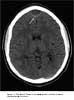

A head CT scan without contrast demonstrated an epidural abscess posterior to the frontal sinuses, with a cortical defect in the posterior wall of the left frontal sinus (Figure 1).